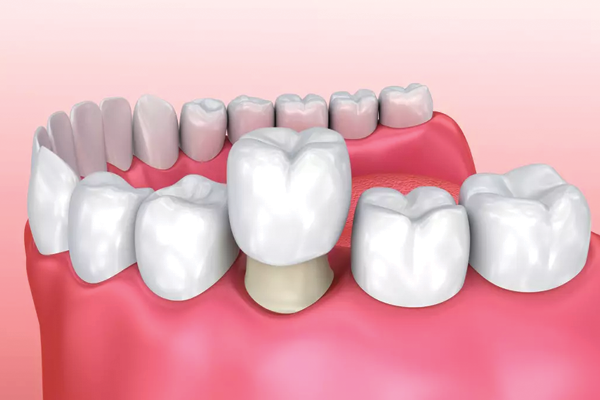

Lorsqu’une dent est tellement abîmée qu’un simple plombage ne suffit plus, la dent peut être renforcée et reconstruite à l’aide d’une couronne. La couronne est en fait un « chapeau » qui recouvre la dent malade.

c’est un type de restauration dentaire qui entoure complètement une dent. Les couronnes sont souvent utilisées pour restaurer la fonction, l’apparence d’une dent après une procédure de traitement de canal ou pour protéger une dent fissurée ainsi que pour en restaurer la forme, la taille et la résistance.

Les principales raisons d’obtenir une couronne dentaire (également appelée “capuchon”) sont les suivantes : réparer une dent cassée, empêcher une dent de bouger, masquer une décoloration, protéger une dent faible contre la casse, modifier la forme d’une dent, arrêter le grincement des dents et améliorer votre sourire.